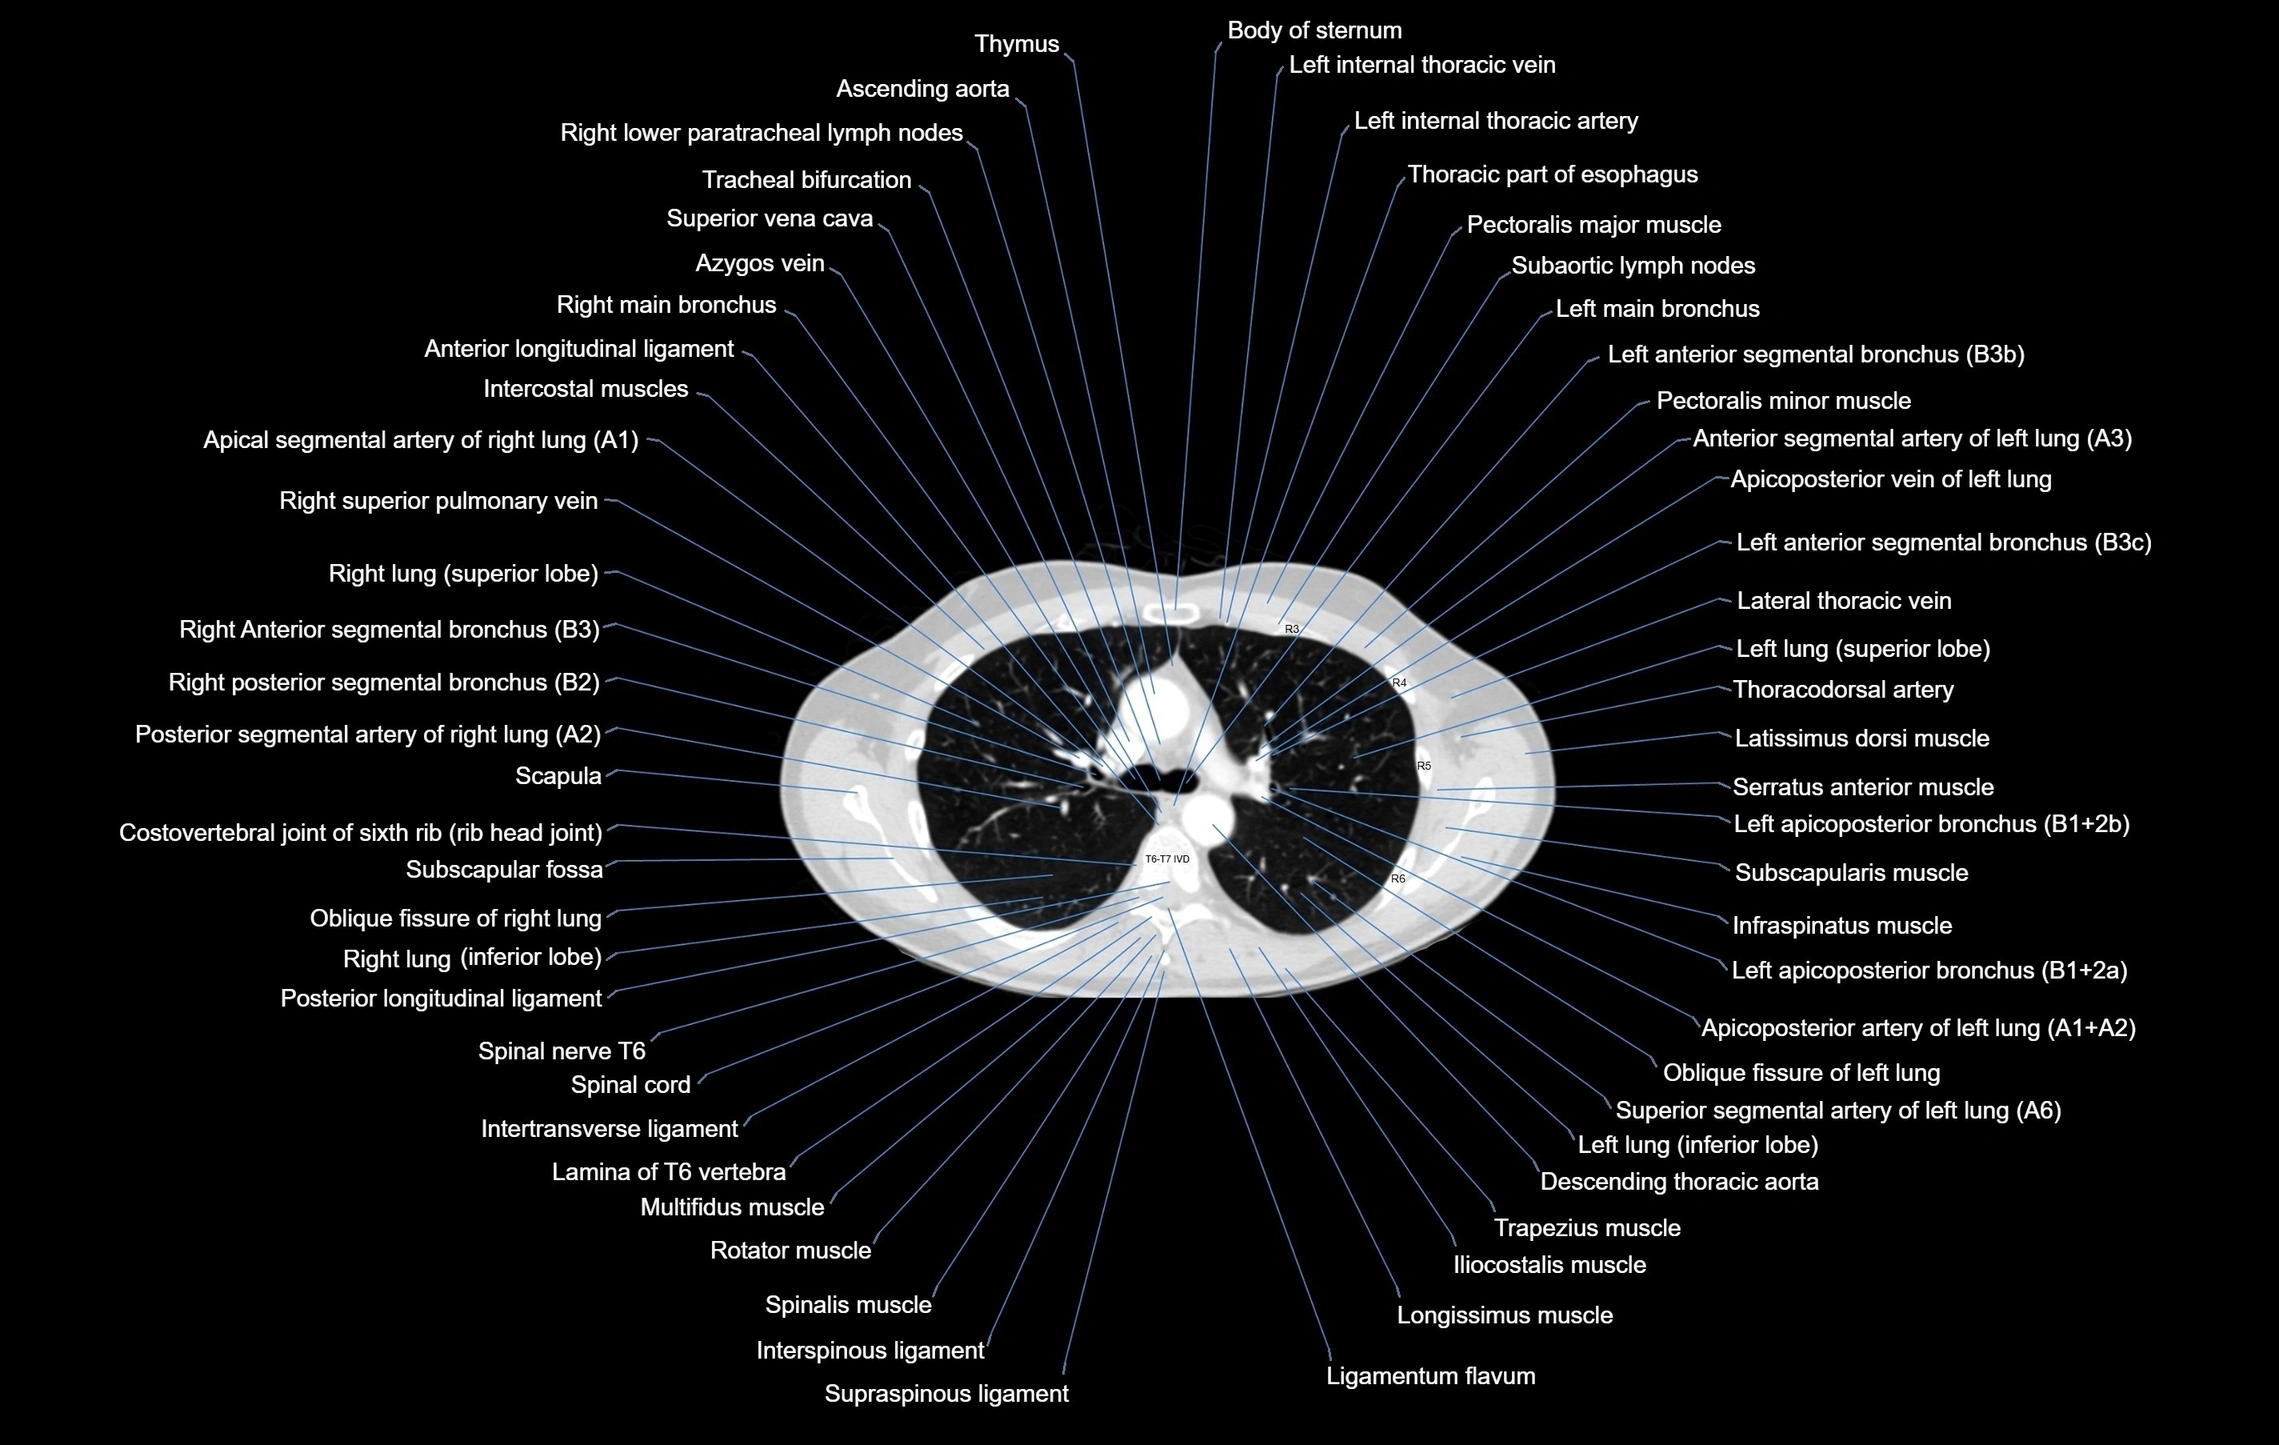

CT images